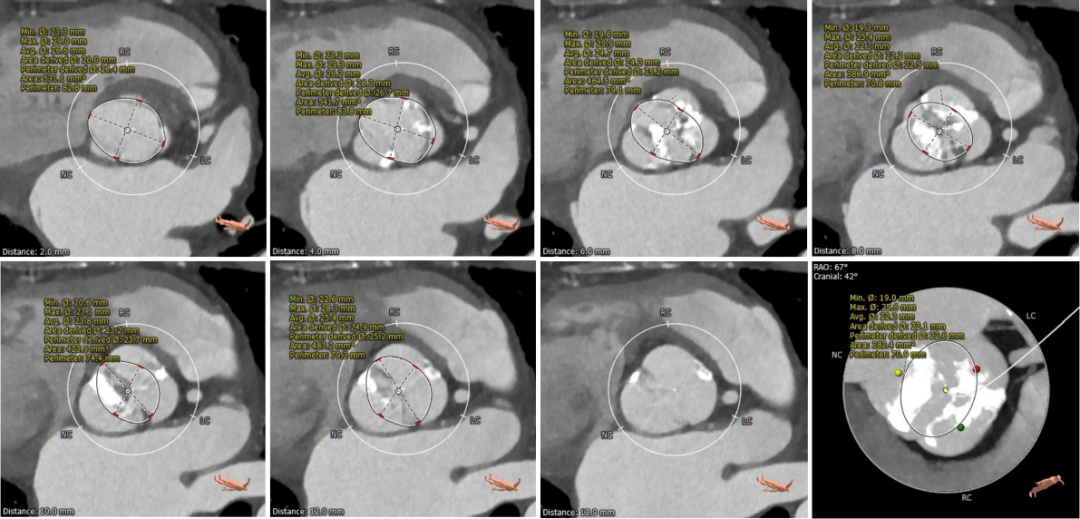

术前CT评估

• Type1型二叶式主动脉瓣,重度钙化,钙化分布稍欠均匀,左右瓣叶融合形成钙化嵴,无瓣叶严重钙化,无冠窦较大;

• 左右冠开口高度可,未见明显冗长瓣叶,冠脉散在钙化;

• 流入段形态呈直桶状,瓦氏窦,窦管交界及升主动脉内径可;

• 主动脉瓣环与水平面夹角可,非横位心,主动脉弓角度与宽度可;

• 入路血管块状散在钙化,双侧股动脉穿刺区域散在钙化,左侧髂外动脉管径稍偏细,右侧入路血管内径尚可;

CT动态预览

主动脉根部测量

瓣上结构测量与分析

冠脉阻挡风险及钙化评估

外周血管入路评估